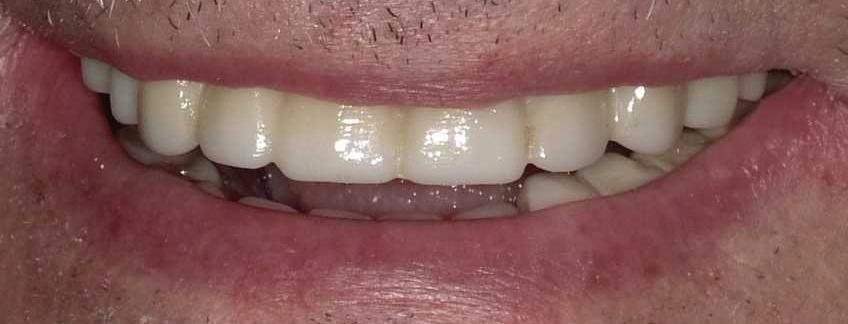

Submitted By Sivakumar Sreenivasan, DMD, MDS Dental Implant Center of Rockville

Can just four implants replace all of the teeth on the top or the bottom of your mouth? Thanks to advances in dental implant technology, that answer is a resounding yes.

Tooth loss is extremely common among adults, especially as we age. Rather than living with the discomfort and hassles of dentures, many people are opting for what is called “all-onfour” dental implant restoration.

An implant is a small titanium

screw that fits inside your jawbone and replaces the root-part of a missing tooth. Minor surgery is required to insert the implants. Once the implant is in place, a crown is attached to give you a highly realistic-looking and functional prosthetic tooth.

You do not need a dental implant for each and every one of your missing teeth. All you need is four precisely placed implants on the top of your mouth, and four on the bottom, to restore your full smile. That’s the beauty of the all-on-four. And because the implant is made of titanium, it has the unique ability to fuse to living bone and function as part of it. So eventually, the dental implant becomes part of the jawbone and serves as a strong, long-lasting foundation for your new teeth.

Besides ensuring that your implants are permanently fixed in place, this bone fusion has another important benefit: it prevents future bone loss in the jaw. This helps to maintain a more